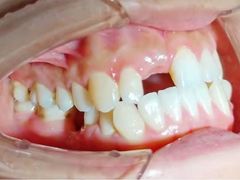

• 联合口腔(西环诊所)

• -联合口腔(西环诊所)

Enemies_6983 | 21-05-09

报错